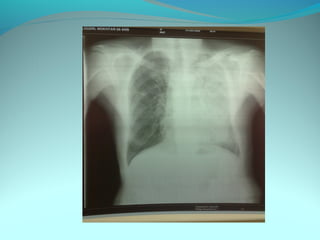

Image radiologique bilatirale a type d’opacité nodulaire occupant les

2/3 sup du poumon droit et la ½ sup du P G confluante par pour

former de grosses opacités

DIAGNOSTIC:

Tuberculose pulmonaire bilateral

Pneumonie bilaterale